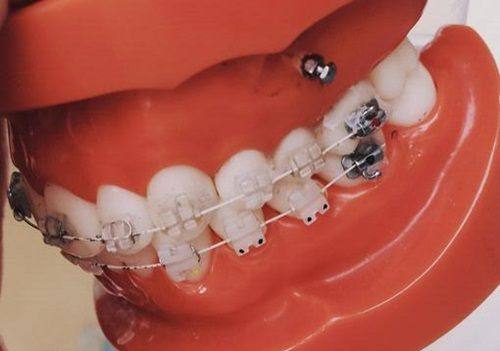

(二)北京有来口腔医院矫正牙齿价格表:

1. 金属托槽牙齿矫正价格:4500元起

2. 金属自锁托槽矫正价格:5500元起

3. 陶瓷半隐形矫正牙齿价格:6500元起

4. 正雅隐形矫正牙齿价格:7500元起

5. 时代天使隐形矫正牙齿价格:9000元起

6. 隐适美矫正牙齿隐形价格:15000元起

7. 舌侧隐形矫正牙齿价格:20000元起

北京有来口腔医院价格表矫正牙齿多少钱?北京有来口腔医院矫正价格4500元起,“元起”源于矫正方式、牙套品牌、矫正难度差异——金属托槽是经典性价比之选,隐形矫正(如隐适美)因美观性和舒适度高,成本高于传统托槽;若患者存在重度牙齿拥挤、咬合畸形,需延长治疗周期或增加辅助装置,价格会有所上升。